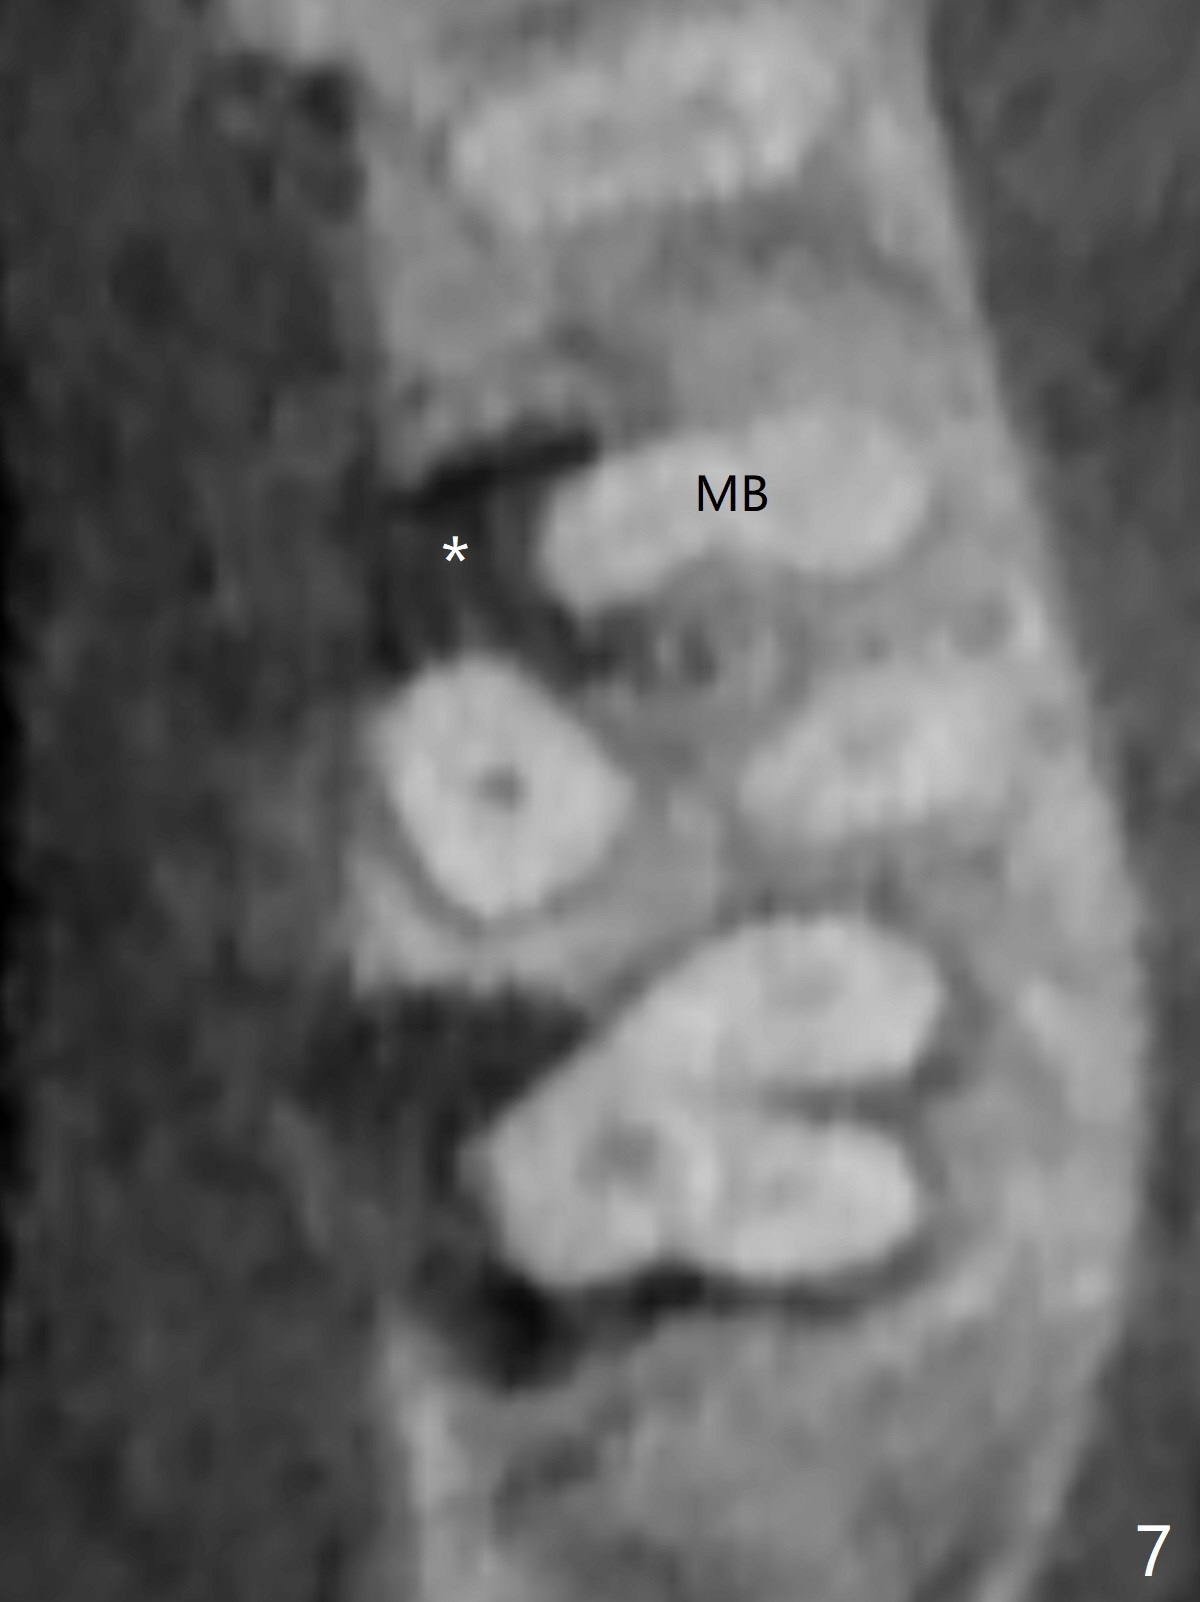

A 60-year-old man had buccal furca abscess at #14 with an unknown radiolucent lesion within the tooth five months earlier (Fig.1 *). Now the tooth is sensitive to cold. CBCT shows internal resorption involving the mesiobuccal and distobuccal roots (Fig.3,4 (axial section) *) with exits mesially (Fig.3 >) and buccally (Fig.2 ^). There is periapical radiolucency of MB (Fig.3,7) with the thickened overlying sinus membrane (Fig.3,5,6 (*), as compared to that over the tooth #3 (Fig.6)). Osteotomy will be established in the septum away from the lesion (Fig.8 red circle) and for 5 mm (Fig.5 (coronal section)). He is a heavy bruxer, loosening Ketac-cemented unipost. Use PRF to repair the defect associated with the MB lesion and sinus lift.